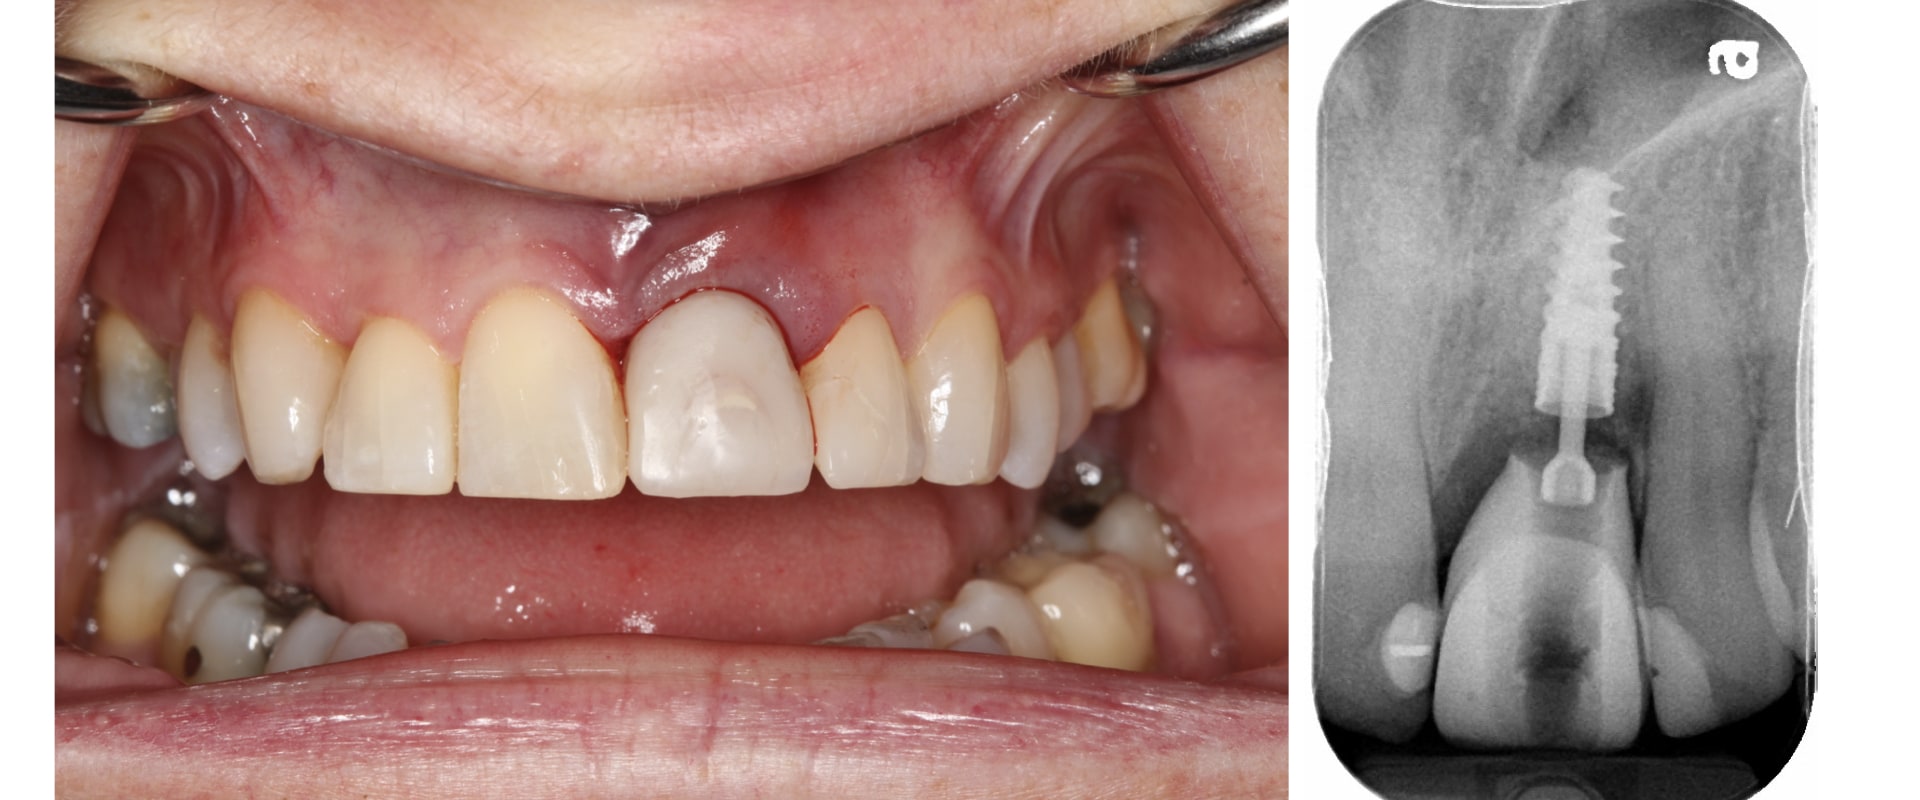

From www.midtownendodontistnyc.com

Root Canal Before & Afters Midtown Endodontist NYC Does A Prosthodontist Do Root Canals While general dentists can also perform root canals, they are not as trained and experienced as endodontists. crowns are commonly used for teeth that are cracked, worn down, or vulnerable after a root canal treatment. a prosthodontist is a dentist who specializes in the restoration and replacement of missing or damaged teeth and tissues of the mouth,. A. Does A Prosthodontist Do Root Canals.